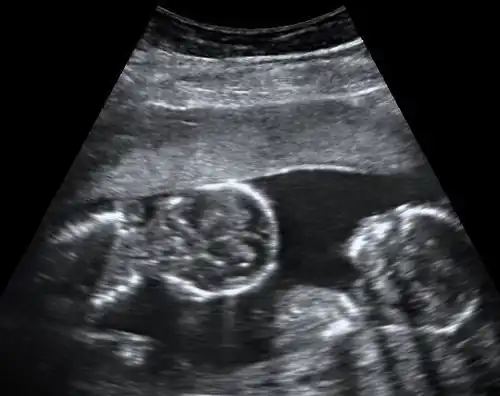

Ultrasound is the only way to detect monoamniotic-monochorionic twins before birth.[4] It can show the lack of a membrane between the twins after a couple of weeks' gestation, when the membrane would be visible if present.[4]

Further ultrasounds with high resolution doppler imaging and non-stress tests help to assess the situation and identify potential cord problems.[4]